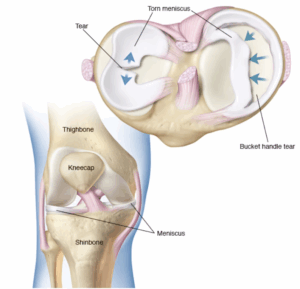

Torn Meniscus

A torn meniscus is one of the most common knee injuries. Any activity that causes you to forcefully twist or rotate your knee, especially when putting your full weight on it, can lead to a torn meniscus.